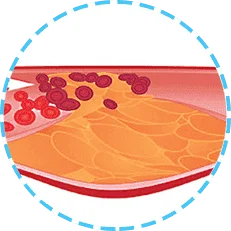

Las placas se asientan en las paredes de los vasos y no permiten la circulación sanguínea o la obstruyen completamente.

Al no recibir la suficiente sangre y oxígeno, el órgano deja de funcionar y como resultado se produce un infarto o un derrame cerebral.

La hipertensión no solo es la elevación de la presión que puede bajarse tomando una capsula. Es un estado en el cual los vasos sanguíneos se estiran y se adelgazan y en sus paredes aparecen sedimentos de colesterol. Como resultado, esto conduce a una interrupción del flujo sanguíneo y al mal funcionamiento de uno u otro órgano.